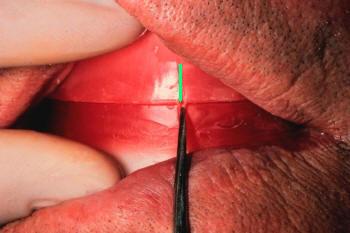

- Realice escotaduras en "V" en el rodete

inferior y superior de 3 a 5 mm de profundidad; siempre de tras de las marcas

de las guías caninas. (Ver imagen inferior)